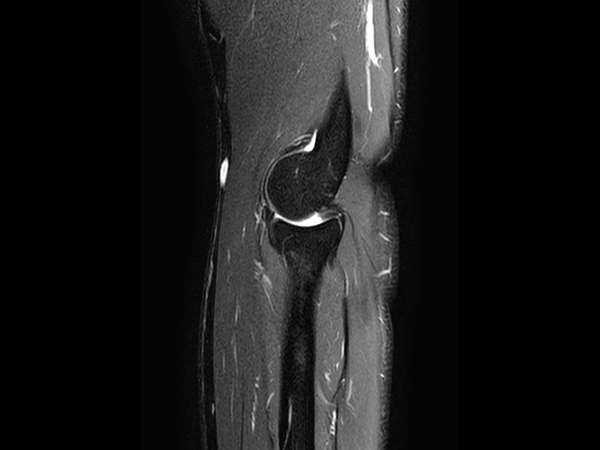

High quality Elbow imaging with Compressed SENSE

Spital Uster, Switzerland